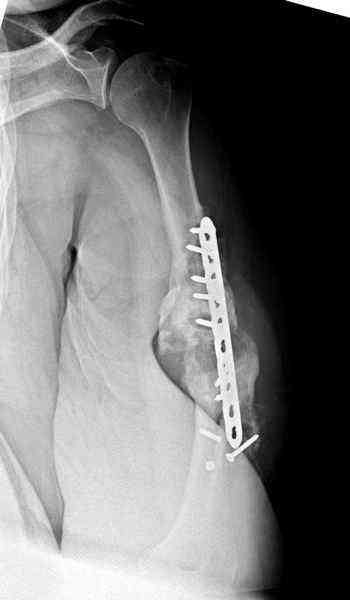

Как видно из выступлений коллег, способы фиксации

ложного сустава плеча могут быть различными, кто-то предпочитает аппаратом Илизарова (Соломин), пластинами (Волна) или интрамедуллярным гвоздем (Челноков).

Когда разбирался случай на сайте, и у нас была больная с похожей патологией, ложный сустав после поперечного перелома, леченного год назад где-то и кем-то в другом месте.

Первичную пластину убрали недели 6 назад из переднего оригинального доступа, и из-за подозрительности тканей вокруг пластины, решили провести реконструкцию поэтапно.

Хотя сам не стороннник применения более массивных

имплантов для плеча, но для этого случая сделали

исключение. На снимке 4А диаметр мягких ткани около 20 см, при весе больной более 135 кг, и также выступление Андрея Волны подстегнуло к применению более массивной 4.5 мм локинг пластины.